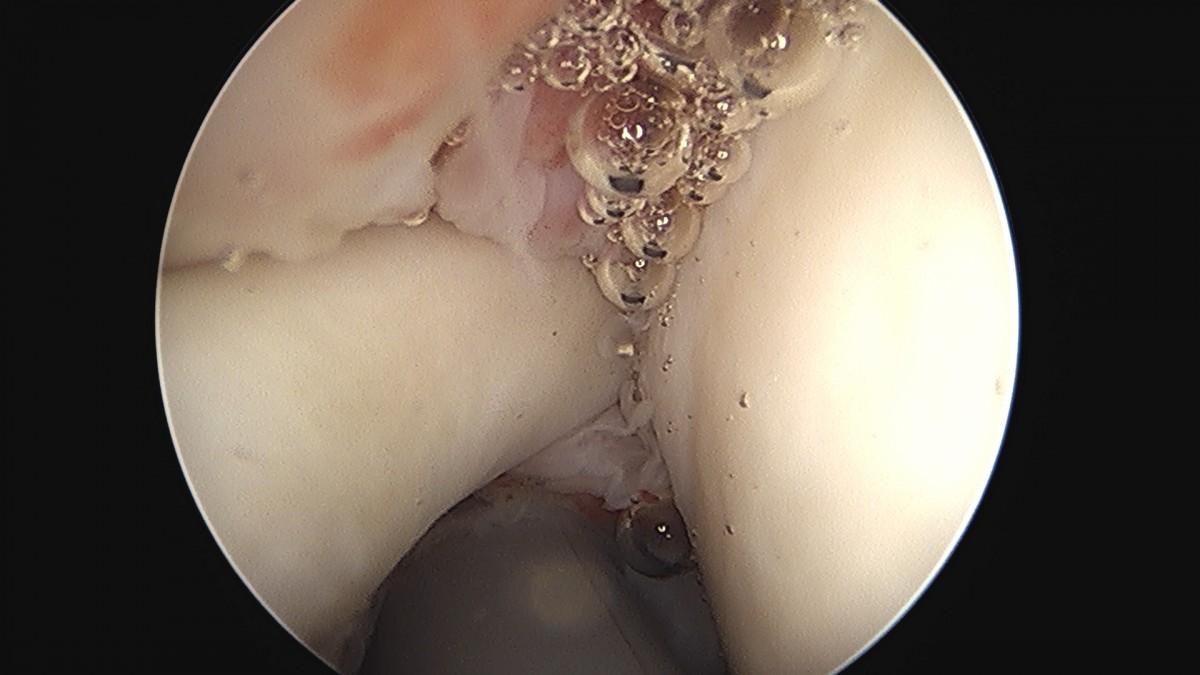

이재상원장님 어깨 견봉하 감압술 김선O 환자

dae765e4d9ac96aee867c9d6292d8784_1758004050_0559.jpg